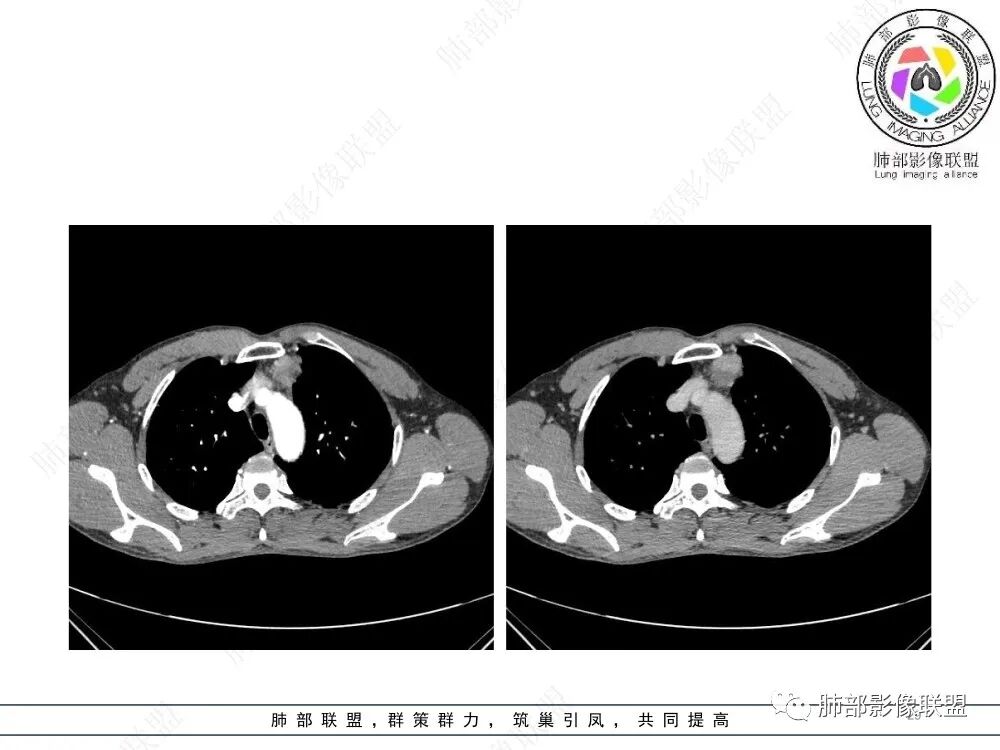

在路上:考虑胸腺瘤,密度均匀,无钙化,轻度强化,边缘请放射线:前纵膈偏左侧肿块,边缘光滑清晰,周围脂肪间隙清晰,渐进性强化,密度不均,考虑胸腺瘤,鉴别淋巴瘤。

良孑:前纵隔肿物,偏心性生长,轻分叶,均勺强化,内可见分格,支持AB型胸腺瘤。

lmg:前纵膈肿块,整体边界整齐,可见AB区,强化不均匀,可见延时强化,病灶内未见明显钙化,无分叶,考虑AB型胸腺瘤。

南边:支持前纵隔、胸腺瘤首选,晨读其实定位上还是有点难度,定性常规还是考虑胸腺瘤,其他的几率比较低一些,需要鉴别的是胸膜SFT,神经源性,可惜的是没重建,一直在犹豫胸膜来源的可能性。

2、影像特点:前纵隔偏左侧软组织影,密度相对均匀,未见明显包膜钙化及实质内钙化,局部边缘浅分叶,周围脂肪间隙密度增高、浑浊,未见侵犯大血管、未见纵隔内淋巴结转移、未见侵犯心包内结构、未见胸膜转移结节、未见肿块沿着纵隔胸膜蔓延,未见胸腔积液。增强后动脉期不均匀强化,未见明显纤维分隔。